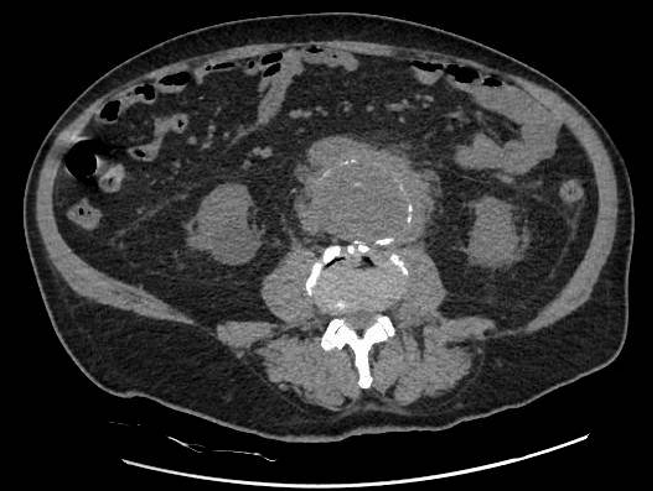

Hombre de 69 años. Antecedentes personales: diabetes mellitus tipo 2, hipertensión arterial, hipercolesterolemia.Acude a Urgencias por astenia progresiva de un mes de evolución y recorte de diuresis. Exploración: palidez mucocutánea. Normotenso y eupneico. Auscultación cardiorespiratoria normal. Abdomen globuloso, blando, no doloroso. Analítica: Hb 9 (previa 11 dos meses antes), urea 160, creatinina 10,9 (previa 1,7), proteína C reactiva 120. Resto anodino (no leucocitosis ni alteraciones iónicas, urianálisis negativo). EFNa: 14% (posrenal). Ecografía renal, que evidencia hidronefrosis bilateral grado III, sin causa obstructiva aparente. Dada la evolución tórpida pese a sueroterapia y diuréticos, se realiza TAC abdominal para continuar estudio de la causa obstructiva: aneurisma de aorta abdominal infrarrenal, con rotura contenida por hematoma y compresión extrínseca de ambos uréteres.

Juicio clínico: Rotura contenida de aneurisma de aorta infrarrenal, comprensión extrínseca ureteral bilateral e insuficiencia renal aguda secundaria.

Monitorización hemodinámica. Se traslada a quirófano de forma urgente para colocación de endoprótesis por vía femoral.